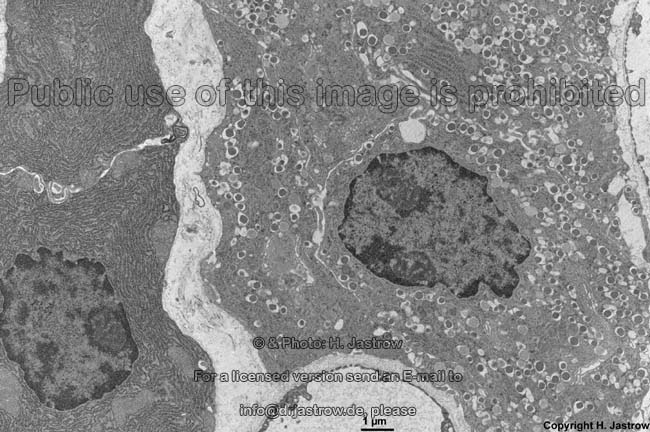

endocrine and exocrine

pancreas (monkey)